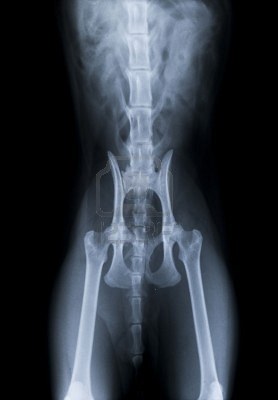

La radiographie permet de visualiser les os et certains organes

La radiographie est le moyen d'imagerie médicale le plus ancien. Cet outil permet de visualiser un certain nombre des structures internes tels que :

- les os et leurs éventuelles fractures

- le cœur et certaines de ses déformations

- les poumons et les opacifications pathologiques

- les intestins

- d'eventuels foetus et leur nombre sur chienne et chatte gestante de plus de 45 jours

Si la plupart du temps, les radiographies peuvent être réalisées sur l'animal éveillé, d'autres nécessiteront une "tranquillisation" afin d’éviter que le sujet ne bouge.